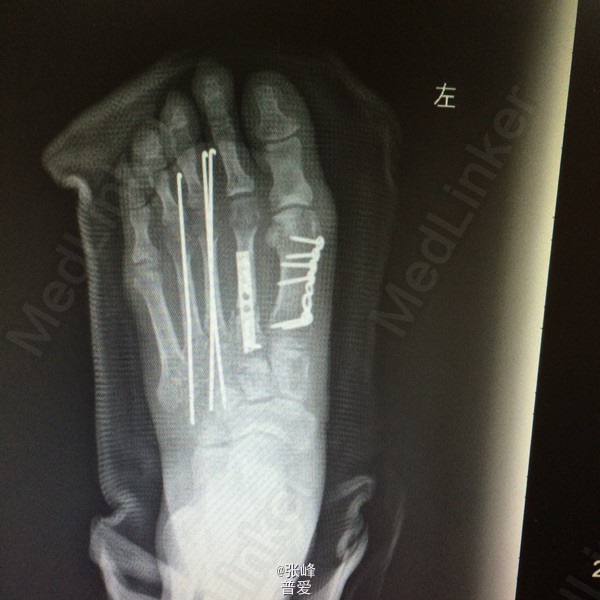

初步诊断: 左跖骨骨折 诊疗计划:1.完善相关检查(血、尿分析、肝肾功能、术前五项、ECG等)。 2.患肢抬高、消肿、冰敷、止痛等对症治疗。 3.择期手术治疗(左足跖骨多发性骨折切开复位内固定术)。

术后恢复好,第一个月复查后取了石膏,功能锻炼恢复了,行走正常,一年后取出内固定